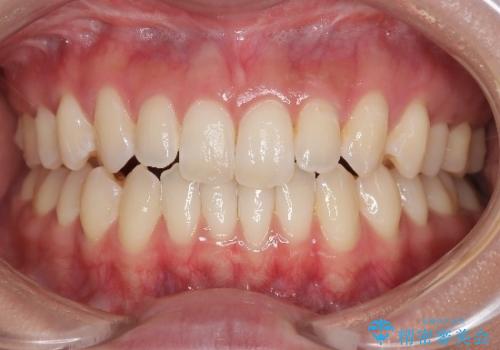

凸凹を綺麗にしたい。表側ワイヤー矯正

担当医 河口智英